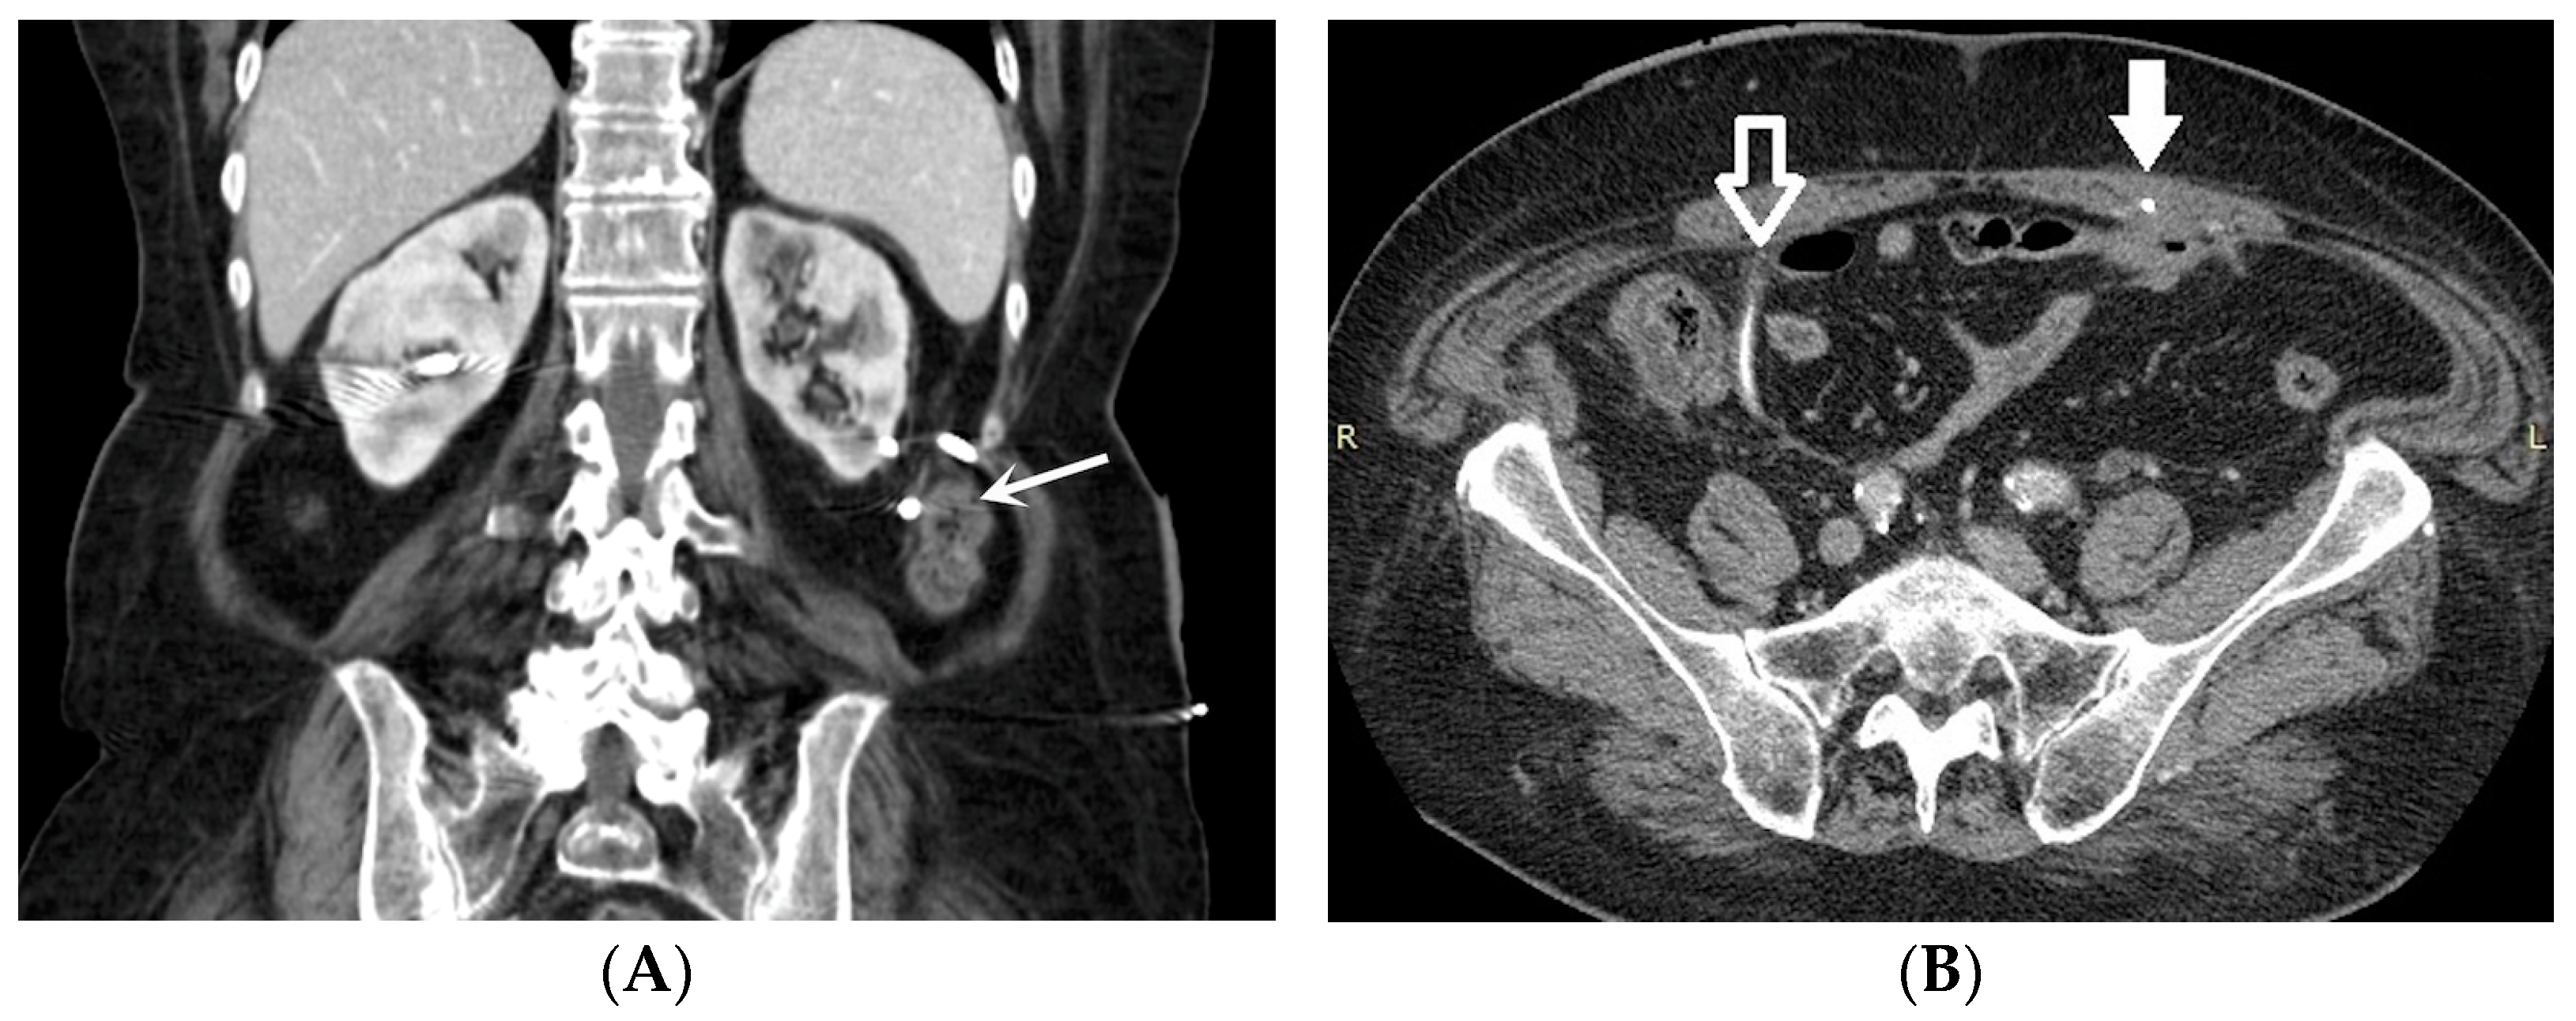

- Bleeding: The erosion of the stent into the arterial system is a rare and feared complication of ureteral stent placement, which can cause hematomas (Figure 10 and Figure 11), active bleeding, or pseudoaneurysm (Figure 12, Figure 13 and Figure 14). To avoid mortality from these complications, a high level of clinical suspicion is essential. Intermittent hematuria in a patient with a stent is typically the usual clinical scenario. However, massive hematuria and circulatory collapse can occur due to the manipulation of the ureteral stent [2,39].